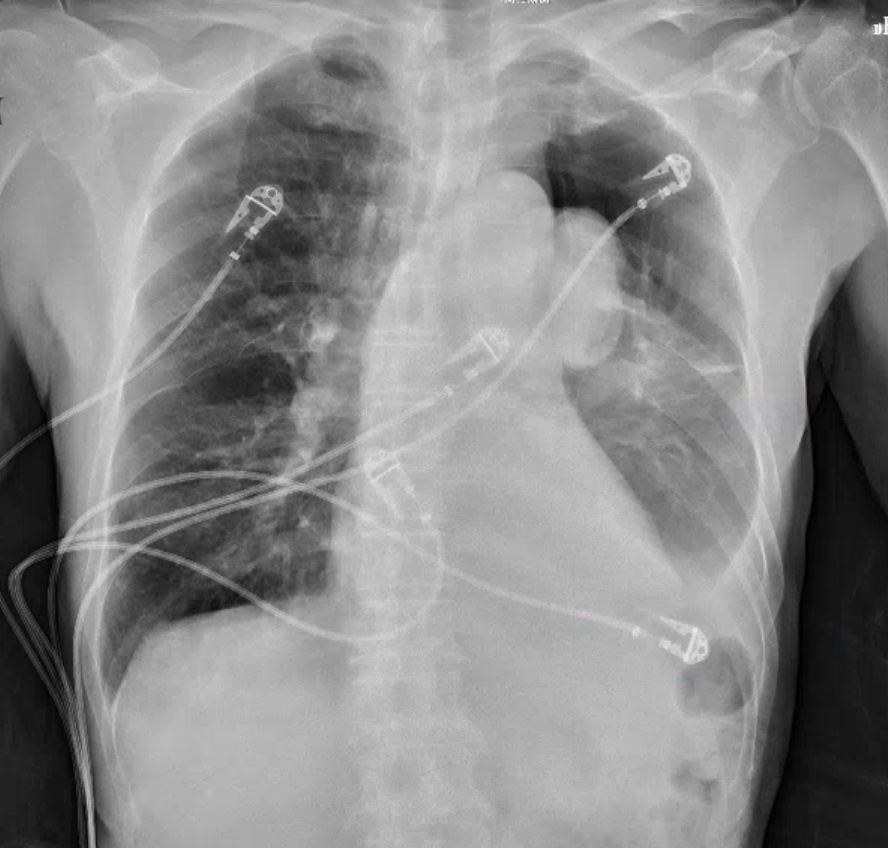

A 71 year old male presents with a chief complaint of dyspnea on exertion. He appears to be in no distress. His vital signs are stable. A CXR is ordered. What's the diagnosis? (scroll down for answer)

Answer: Pneumothorax secondary to bleb rutpure

- This CXR demonstrates a spontaneous pneumothroax contained to the left upper lobe secondary to bleb rupture